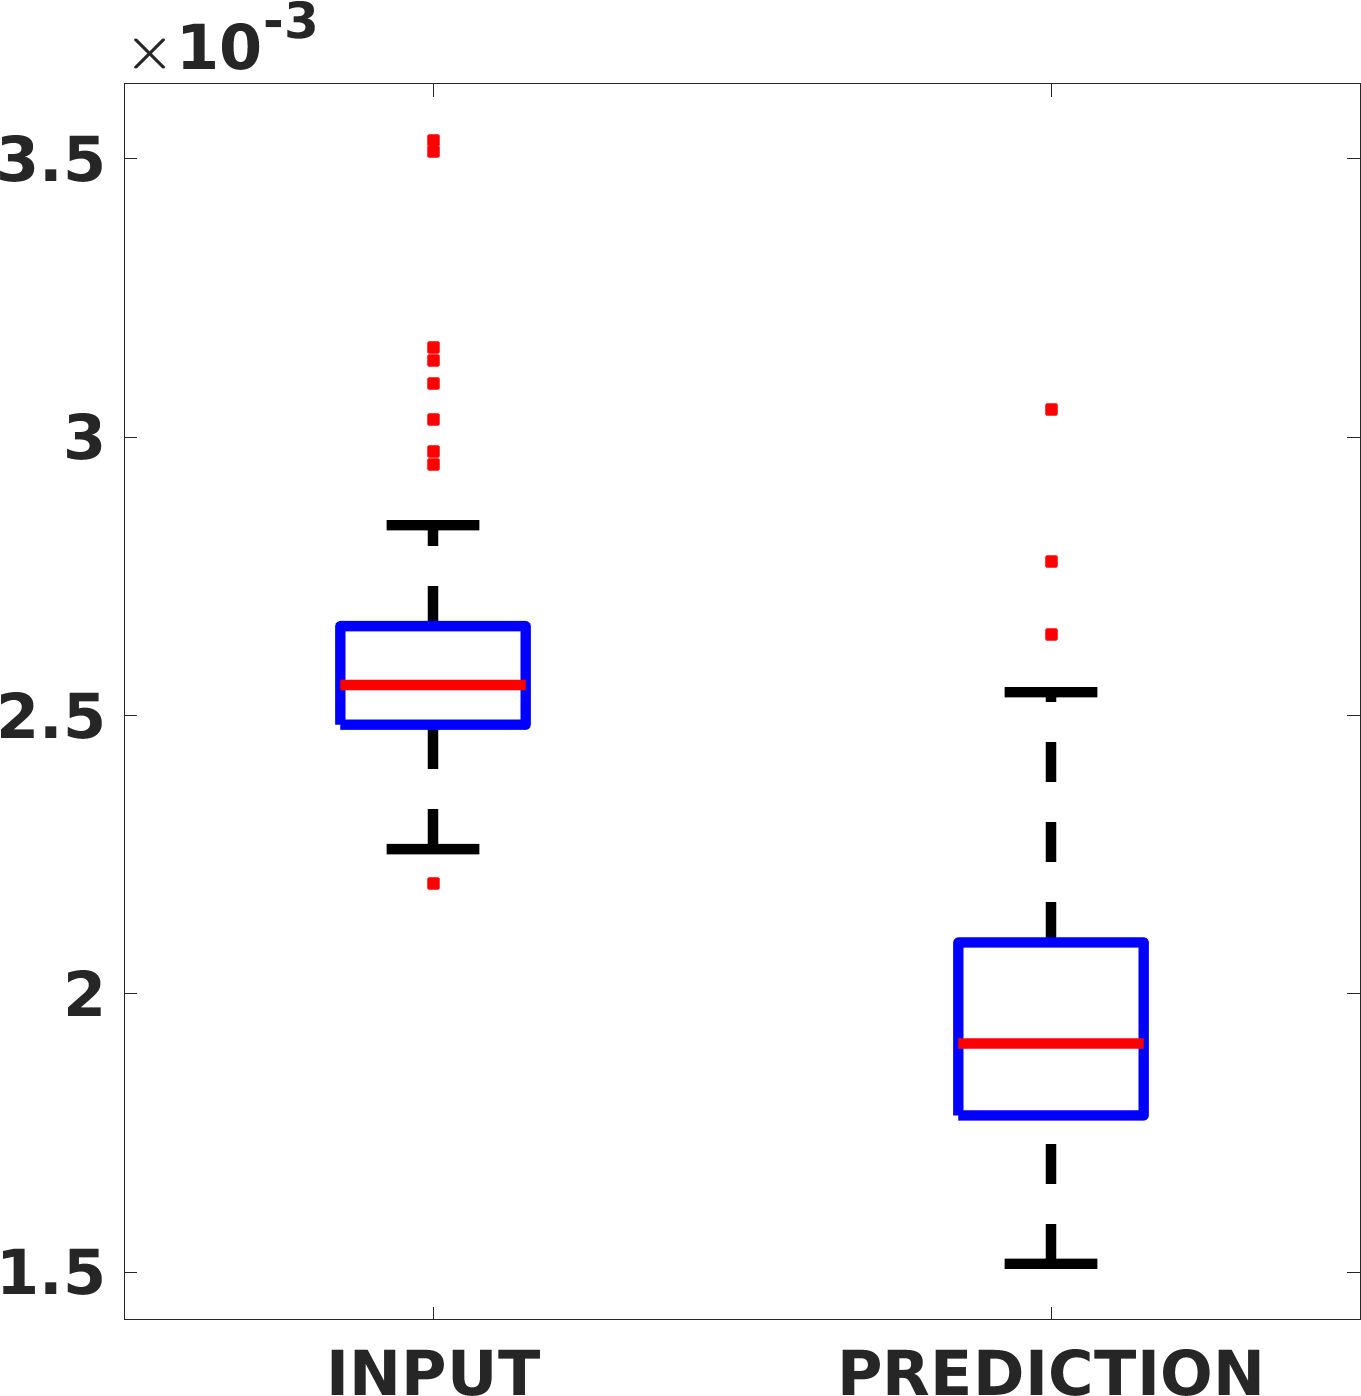

Fig. 8 shows the box plot of the SSIM (a-b-c, left) and MAE (a-b-c, right) quantitative metrics, as performed for PSNR metric. Also, these metrics show that our method improves the results of Cubic convolution both in terms of average value and variability. For example, the SSIM median value improves of on obstetric 4X images and the MAE median value improves of on cardiac 2X images.

Fig. 17 (left) shows the box plot of the quantitative metrics, comparing the target images with the prediction and the Cubic convolution, respectively. The PSNR metric is computed on a data set of 200 images, belonging to the same district, and with the same up-sampling factor. Analysing the obstetric anatomical district and concerning the corresponding raw images (Fig. 7 (a, left)), the denoising allows the network to significantly improve the results of the up-sampling and the prediction. In particular, comparing the target images with the predicted images, the median PSNR value of obstetric 2X denoised images is 51.8, compared to the median PSNR value of obstetric 2X raw images which is 36.9.

Fig. 17 (right) shows the histogram of the absolute value of the error with respect to the target, of the prediction and Cubic convolution respectively. This result shows that our framework increase of and (2X and 4X, respectively) the number of pixels where the prediction error is lower than 5, which is very similar to the target when visually analysing the images, and improved with respect to the learning framework applied to raw images. According to Fig. 18, our method improves the accuracy of Cubic convolution. For example, the SSIM increases of on cardiac 2X and the MAE increases of on abdominal 4X.